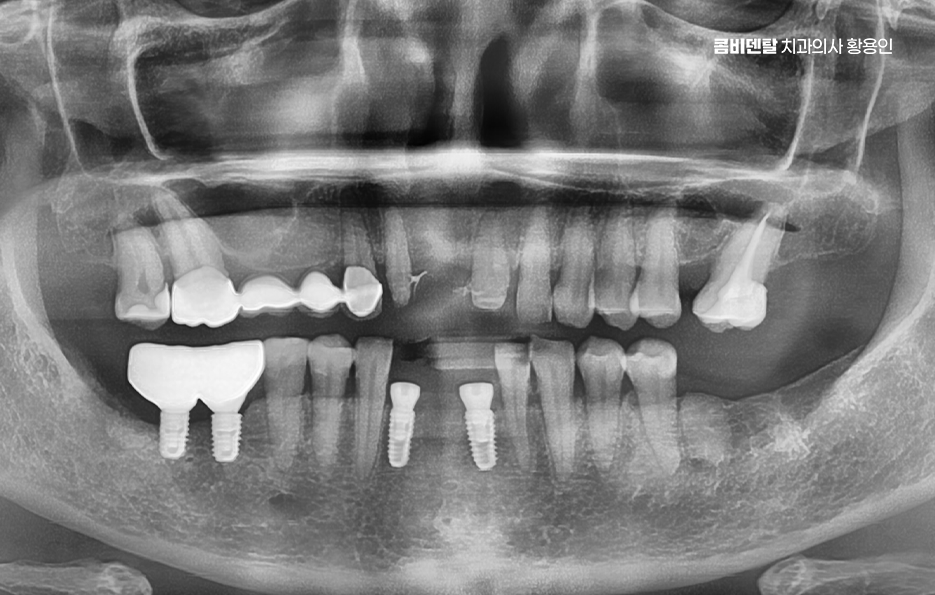

임플란트 치료의 주된 원리는 '골유착'에 있는데 이 단어가 조금 생소할 수 있지만 쉽게 말하면 임플란트의 인공치근, 자연치의 뿌리 역할을 대신하는 인공치근은 티타늄 재질로 구성되어 있고 잇몸뼈 안에 심으며 그 뼈가 이 인공치근을 자기 뼈처럼 감싸서 단단하게 붙는 현상을 말하는 거예요

티타늄은 인체에 생물학적으로 안정적인 금속이라서 뼈가 이물질로 인식하지 않고 잘 달라붙는 성질이 있는 것으로 치조골 안에 이 티타늄으로 구성된 인공치근이 수개월 동안 안정적으로 뼈와 결합되는 과정을 거치게 되면서 자연치아에 버금가는 저작력을 갖추게 되는 것이 주된 치료 원리라고 할 수 있었어요

임플란트의 장점 이 골유착이 완성된 이후에는 그 위에 기둥을 세우고, 마지막으로 보철물을 씌우게 되는데 이렇게 되면 겉에서 보기엔 자연치아와 거의 차이가 없으며 심지어 기능적으로도 자연치아와 유사한 수준의 저작력이 가능해지며 다시 말해 뿌리부터 머리까지 인공치아를 만드는 건데 ‘뼈에 심는’ 것이기 때문에 더 안정적이고 오래 쓸 수 있는 치료인 거예요.

이러한 치료 원리를 토대로 임플란트의 장점을 정리해보면 첫 번째로 큰 장점은 주변 치아에 손상을 주지 않는다는 점으로 예전에는 치아를 하나 잃으면 양 옆의 치아를 깎아서 브릿지를 씌우는 방식이었어요. 문제는 건강한 치아까지 손상시켜야 한다는 점이었고 게다가 브릿지 아래는 관리가 어렵다 보니 2차 충치가 생기기 쉬워서 결국 더 많은 치아를 잃게 되는 경우가 많았던 것인데 임플란트는 해당 부위만 단독으로 치료하기 때문에 주변 치아는 그대로 두고, 본인 치아처럼 기능하게 할 수 있었어요.